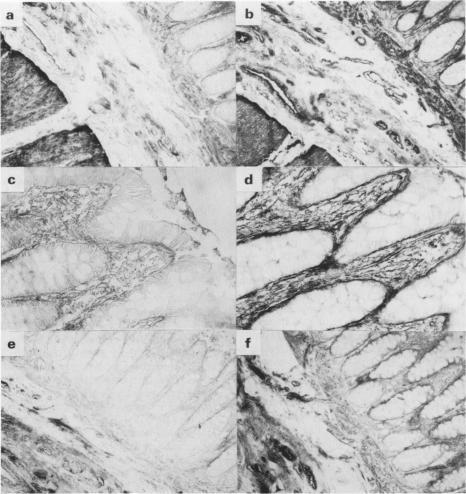

Using an immunoperoxidase procedure, we have examined the distribution of laminin and fibronectin in normal human large intestinal mucosa and in 50 cases of rectal adenocarcinoma for which extensive clinical follow up was available. In normal tissue, laminin staining was largely restricted to basement membranes, including that underlying the epithelial cells, whereas fibronectin was found in both basement membranes and surrounding connective tissue. In rectal carcinomas, basement membrane-like staining for laminin associated with tumour cells was found in only 27 out of the 50 cases studied. Statistical analysis showed that the presence of laminin-containing basement membranes was correlated with low histological grade (well-differentiated tumours), but not with stage (progression through the bowel wall and the development of lymph node metastases) and, in a highly significant way, with a reduced incidence of distant metastases and increased patient survival. Although fibronectin was found in tumour cell basement membranes where these were present, it was also found in the stroma of all 50 tumours. There was no apparent correlation between the presence of stromal fibronectin and grade, stage or development of metastases. Finally, attention is drawn to some of the technical difficulties in detecting basement membrane antigens in formalin-fixed tissue, the material most frequently available for retrospective study.

我们采用免疫过氧化物酶法,研究了层粘连蛋白和纤连蛋白在正常人大肠黏膜以及50例有广泛临床随访资料的直肠腺癌中的分布情况。在正常组织中,层粘连蛋白染色主要局限于基底膜,包括上皮细胞下方的基底膜,而纤连蛋白则在基底膜和周围结缔组织中均有发现。在直肠癌中,在所研究的50例病例中,仅有27例发现与肿瘤细胞相关的层粘连蛋白呈基底膜样染色。统计分析表明,含层粘连蛋白的基底膜的存在与低组织学分级(高分化肿瘤)相关,但与分期(肿瘤穿透肠壁及发生淋巴结转移)无关,且与远处转移发生率降低及患者生存率提高高度相关。尽管在存在肿瘤细胞基底膜的地方发现了纤连蛋白,但在所有50例肿瘤的基质中也都发现了纤连蛋白。基质纤连蛋白的存在与分级、分期或转移的发生之间没有明显关联。最后,需要注意在福尔马林固定组织(这是回顾性研究最常用的材料)中检测基底膜抗原存在一些技术难题。